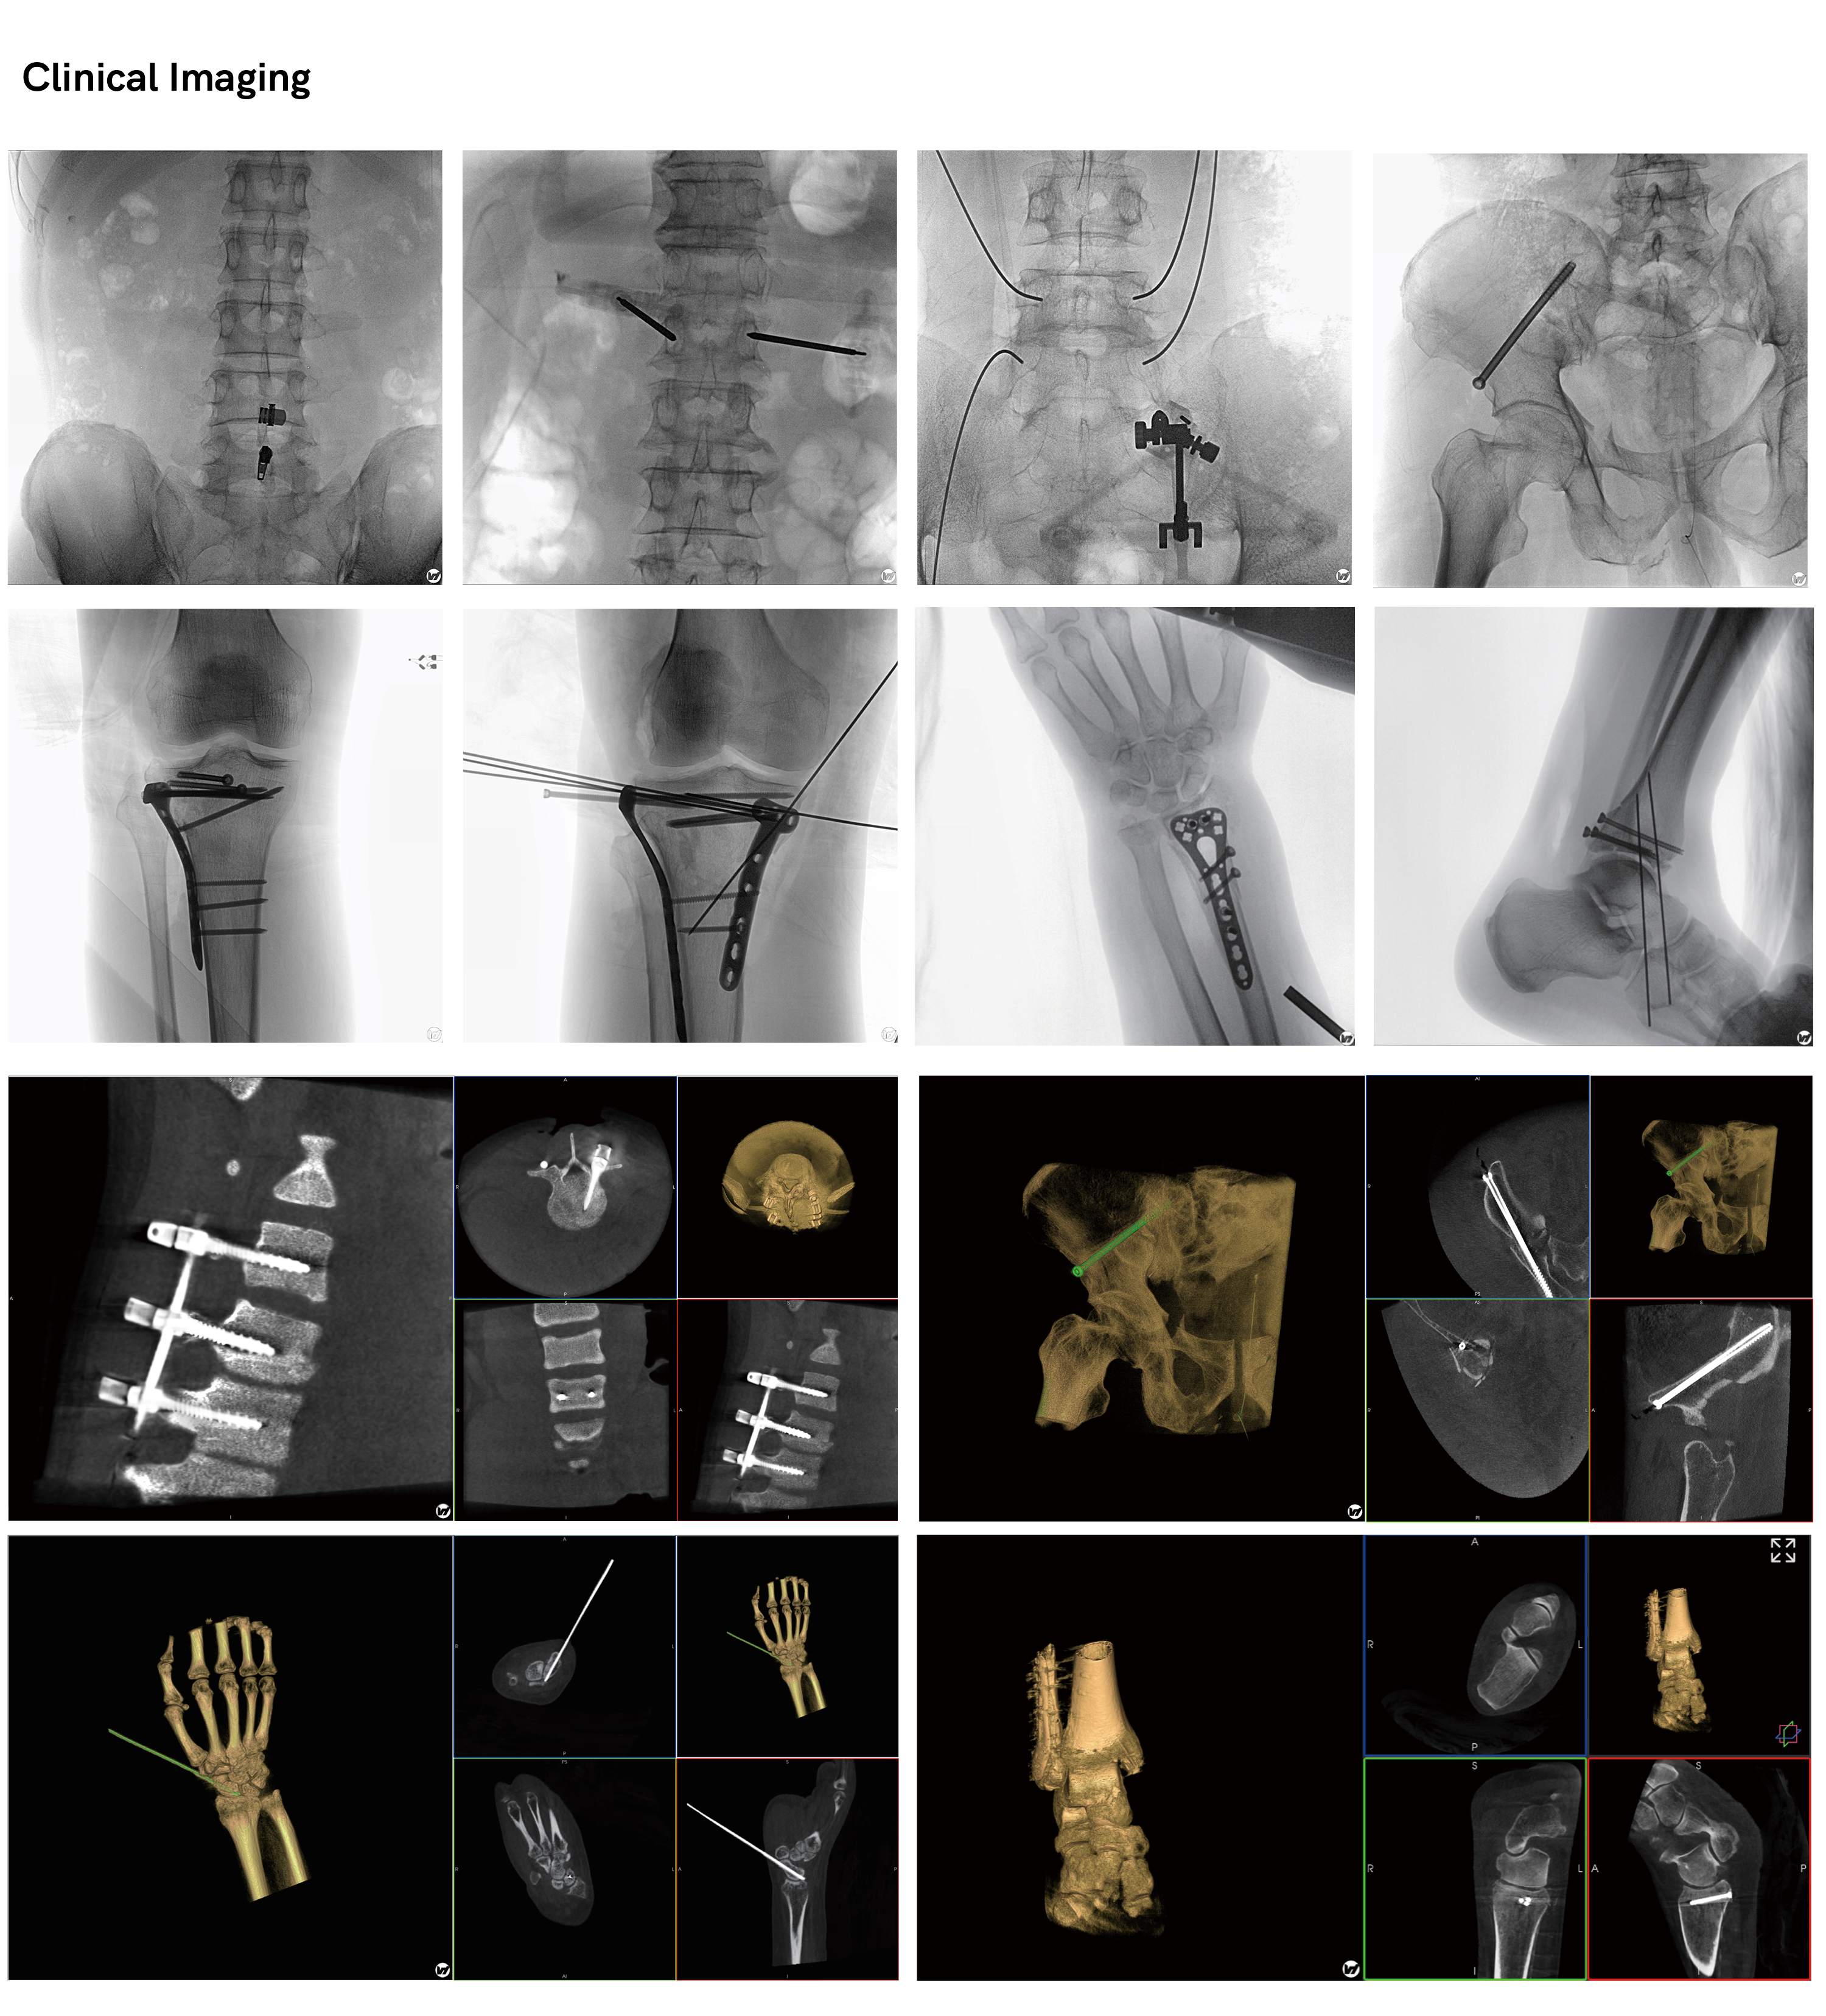

WIL Meta Attain® 3D C-arm

Clinical field

Orthopedic Spine

Orthopedic Trauma

Orthopedic Joint